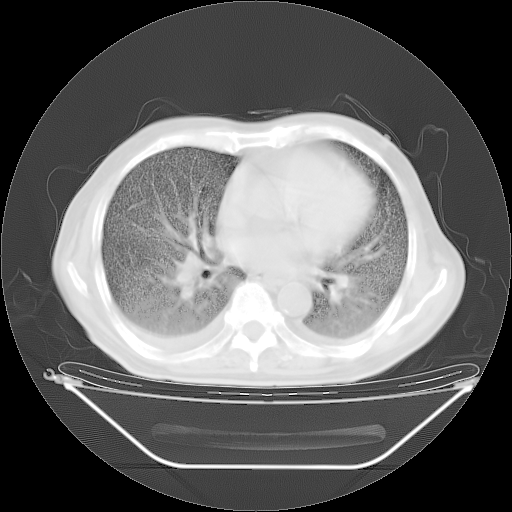

今天复查肺部CT,发现双肺广泛磨玻璃样改变。所以我把3月19日和5月9日相隔50天的肺部CT上传。请大家会诊。

2009年3月19日肺部CT片。

5月9日肺部CT(在4月27日齐鲁医院肺部CT描述部分肺组织磨玻璃样改变,12天后肺组织广泛磨玻璃样改变)